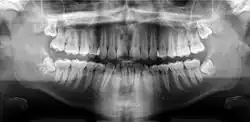

В медицине панорамная томография используется при исследовании лицевого черепа, в первую очередь при диагностике заболеваний зубочелюстной системы. Используя движение рентгеновского излучателя и кассеты с плёнкой по специальным траекториям, выделяется изображение в форме цилиндрической поверхности[1]. Это позволяет получить снимок с изображением всех зубов пациента, что необходимо при протезировании, оказывается полезным при пародонтозе, в травматологии и ряде других случаев. Диагностические исследования выполняют с помощью пантомографических дентальных аппаратов.

В настоящее время при панорамной томографии чаще используют цифровые (компьютерные) томографы ввиду меньшей лучевой нагрузки на пациента при высоком качестве изображения. Существуют также дентальные рентгеновские компьютерные томографы, с помощью которых можно получить трёхмерное изображение челюсти[2].